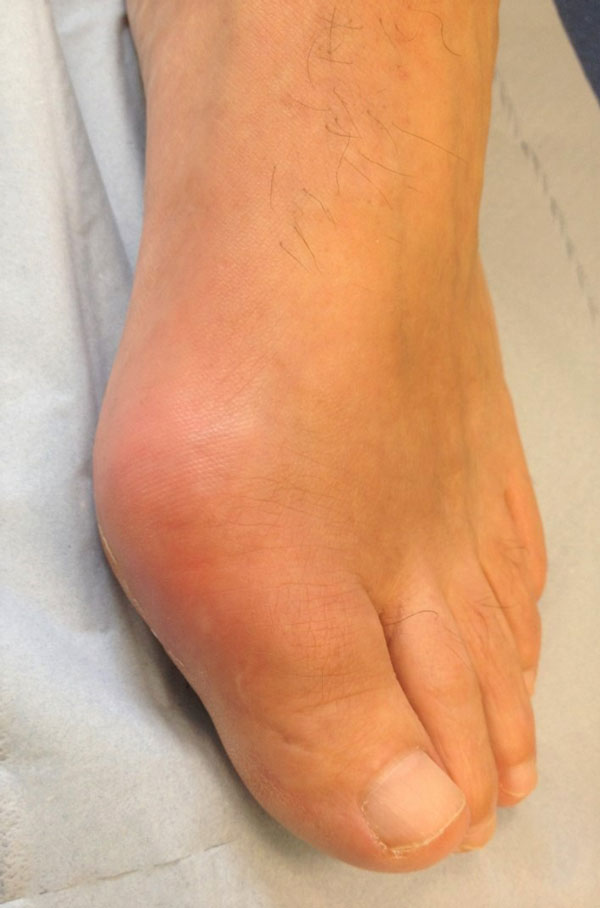

The most common presentation is a gout flare, characterised by acute onset of one, and occasionally more, hot, red, swollen joints which are extremely painful and very tender.22 Peak severity of flares occurs in 12-24 hours. Most flares affect the feet, knees, hands or elbows, although any joint can be affected. Involvement of the first metatarsophalangeal joint, podagra, is very characteristic, see figure 2.22